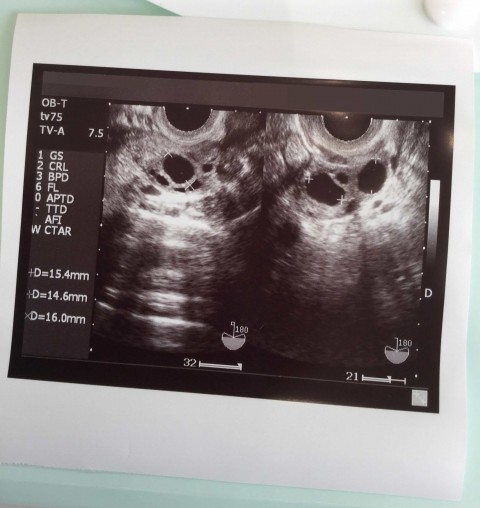

実際に妻が貰ってきた胎児の頃のエコー写真がこれね。

この時は妊娠6週目なんだけど、赤ちゃんの大きさは6ミリ程度で人間の形じゃなく豆のような形だね。

パっと見た感じの印象だと「枝豆」みたいな形だけど、ここから人の形に変わっていくんだよな。

妊娠初期の赤ちゃんは本当に小さくて、枝豆くらいの大きさから1週ごとに成長していくのよ。

そんで次は時間が経過した妊娠19週(5ヵ月)のエコー写真。

この時点で既に人の形になってるのが視認できる。この写真の顔は横を向いてるんだけどさ。

さらに妊娠32週(8ヵ月)における時点のエコー写真がこれね。

お腹の中にいる赤ちゃんを右側から撮影してんだけど、指の形もハッキリしてるでしょ。

産婦人科の先生が分かりやすくボールペンで形をなぞってくれたから、具体的に顔や手の部位が分かるのよ。